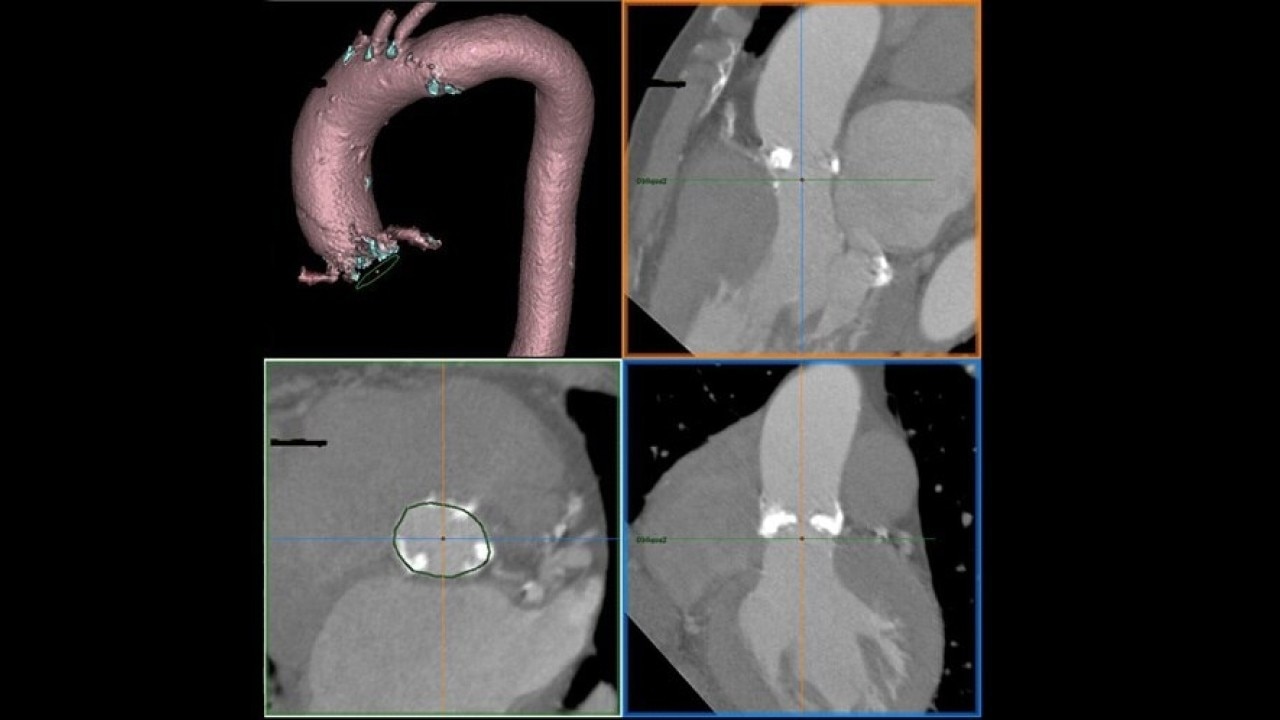

The Valve Planning protocol in the VesselIQ Xpress application lets you visualize cardiac anatomy with the degree of detail required to evaluate the presentation of the aortic valve. Armed with this information, you can develop a pre-procedural TAVR/TAVI plan to establish a therapy strategy for the patient.